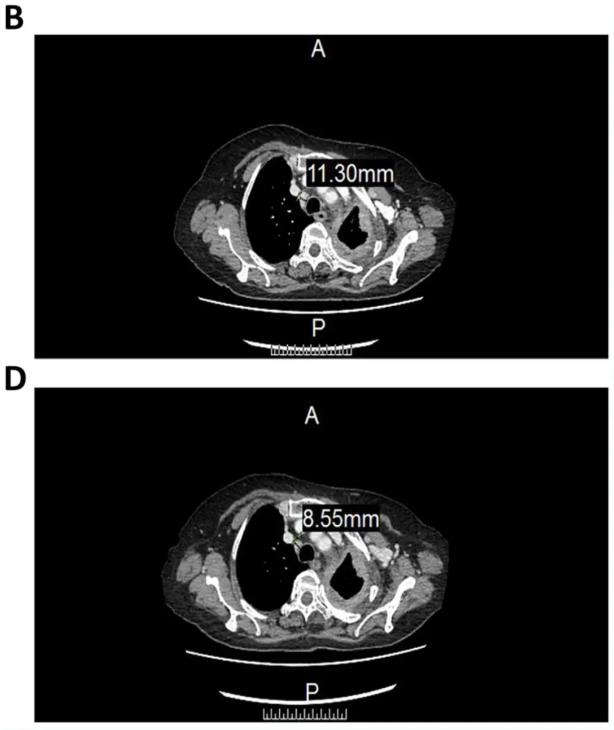

1、患者气管前-后腔静脉间质区的淋巴结,从11.3毫米(mm),缩小至8.55mm(详见下图)。

▲图源“Sage Journals”,版权归原作者所有,如无意中侵犯了知识产权,请联系我们删除

2、患者左肺包裹的胸腔积液,从46.22mm,减少至33.59mm(详见下图)。